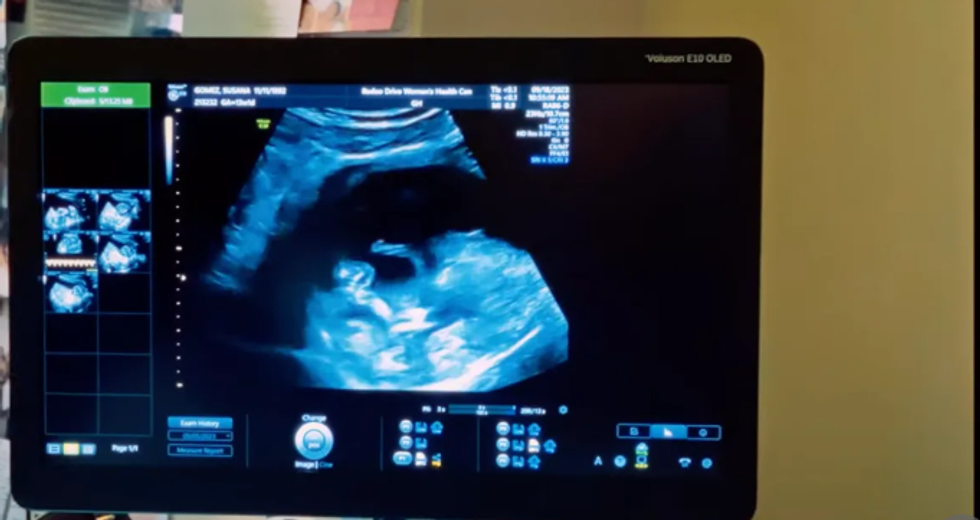

Në video shihet se çifti po përjeton rrugëtimin e shtatzënisë. Nga vizita e mjekut deri tek tregimi i familjes dhe madje edhe ndarja e emrit të fëmijës, prindërit e ardhshëm mund të shihen duke kaluar emocione të ndryshme.

Ata janë në pritje të një vajze të vogël.